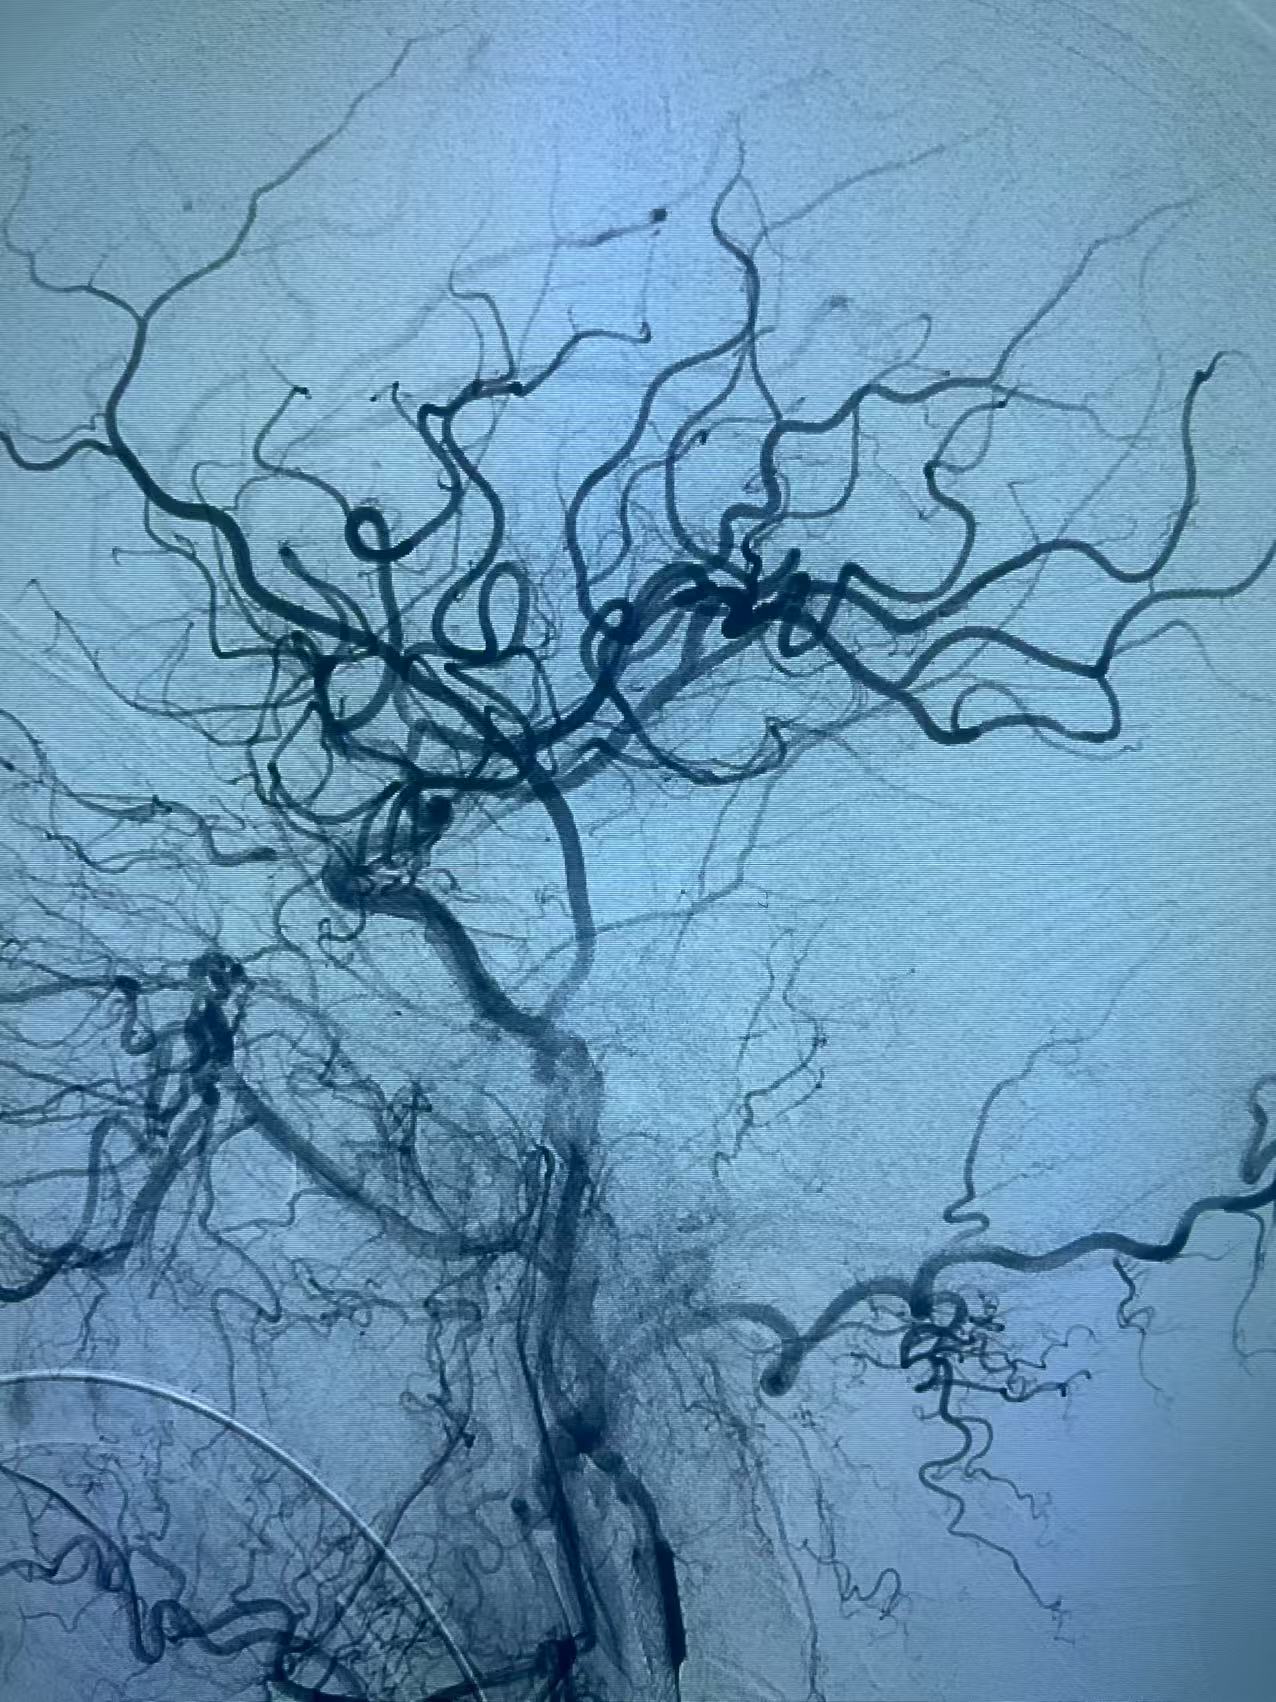

颈内动脉开口重度狭窄基础之上的急性闭塞